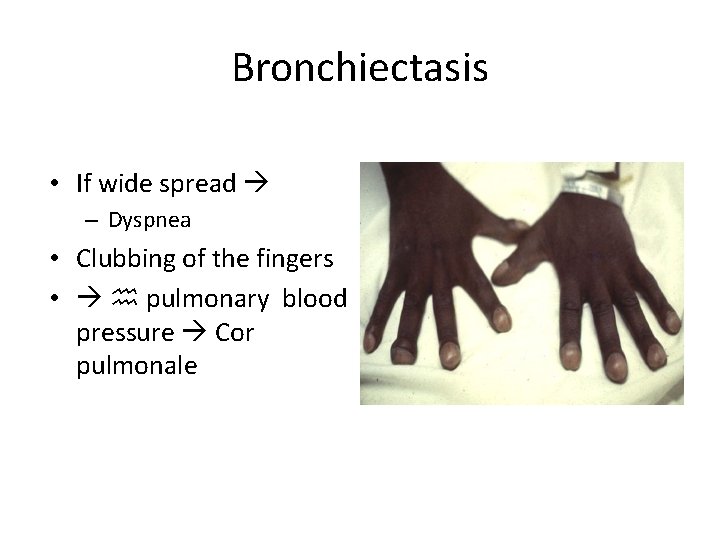

Bronchiectasis • If wide spread – Dyspnea • Clubbing of the fingers • h pulmonary blood pressure Cor pulmonale